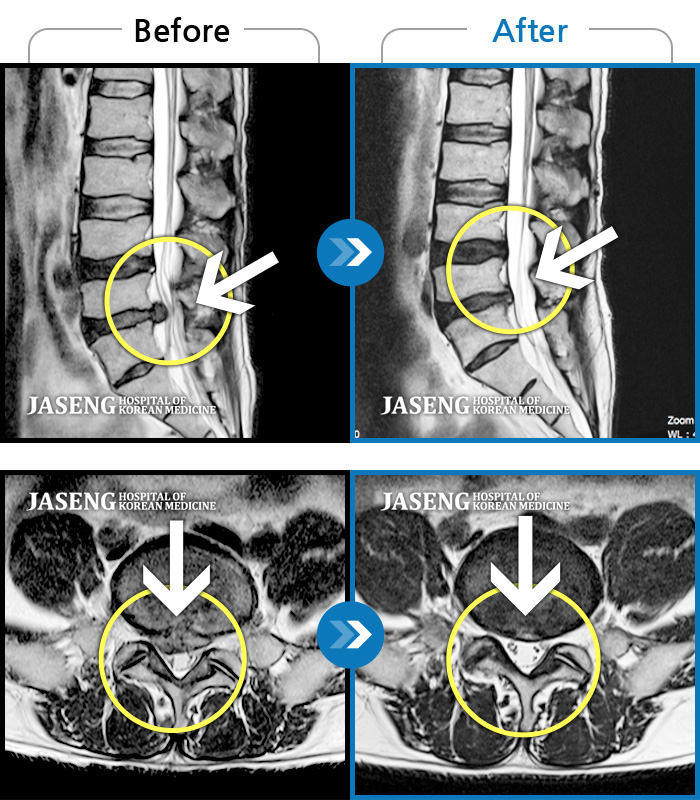

Before

After

환자에게 사전 동의를 받아 동일 조건에서 촬영되었습니다.

개인에 따라 치료 후 부작용이 발생할 수 있으니 의료진과 상담 후 치료를 진행하시기 바랍니다.

허리 통증으로 내원

허리통증 및 하지 방사통